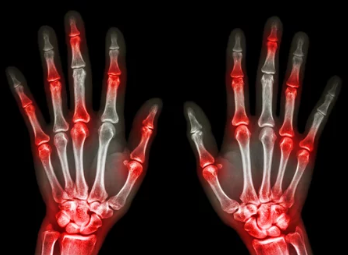

- 엄지발가락 통증: 통풍 초기 증상의 가장 흔한 형태로, 엄지발가락 관절이 빨갛게 붓고 극심한 통증이 느껴집니다. 심한 경우 발가락을 살짝 스치기만 해도 칼로 찌르는 듯한 통증을 느낄 수 있습니다.

- 관절 부위의 발적, 부종, 열감: 엄지발가락 외에도 발목, 무릎, 손목, 팔꿈치 등 다른 관절 부위에도 통풍 발작이 발생할 수 있습니다. 관절 부위가 빨갛게 붓고 뜨거워지며, 심한 통증이 동반됩니다.